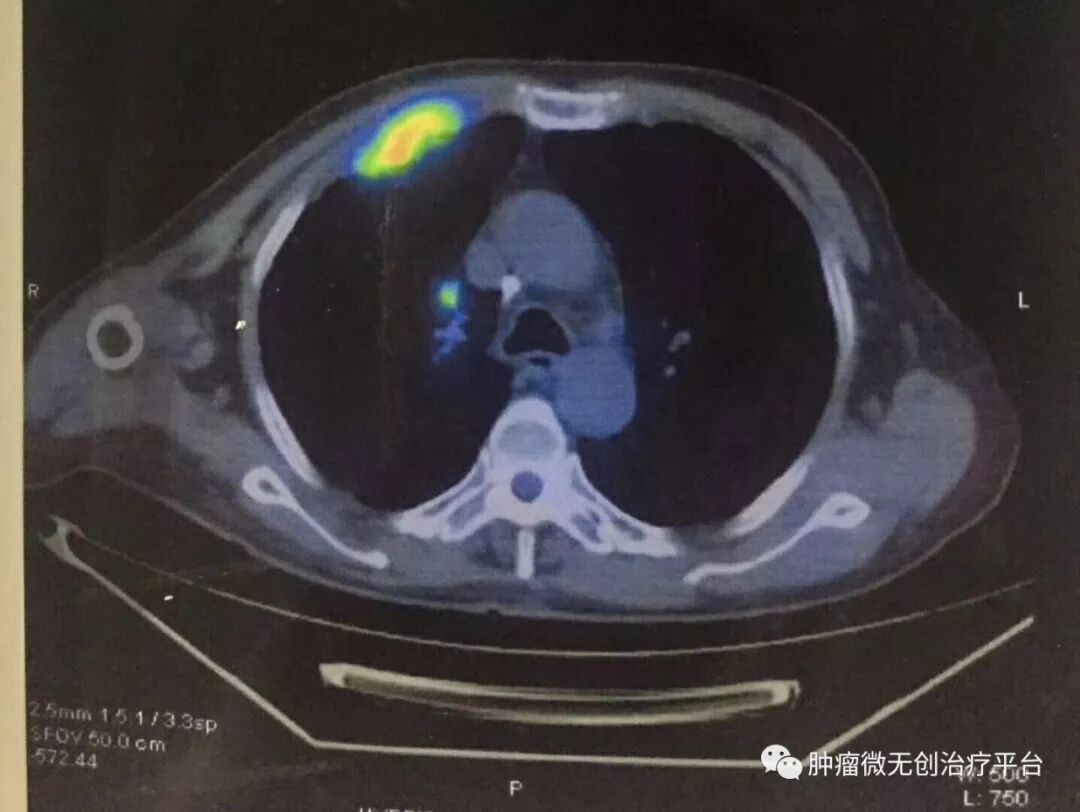

正文:5月28日,右肺腺癌侵犯胸壁患者,在天津市武清区中医医院胸外科进行氩氦刀冷冻消融治疗。

患者情况高龄(79岁)右肺腺癌侵犯胸壁患者肿瘤供血动脉栓塞➕氩氦刀冷冻消融术:图1-2术前PET-CT;图3术前CT;图4-5肿瘤供血动脉栓塞介入;图6-9氩氦刀冷冻消融治疗。